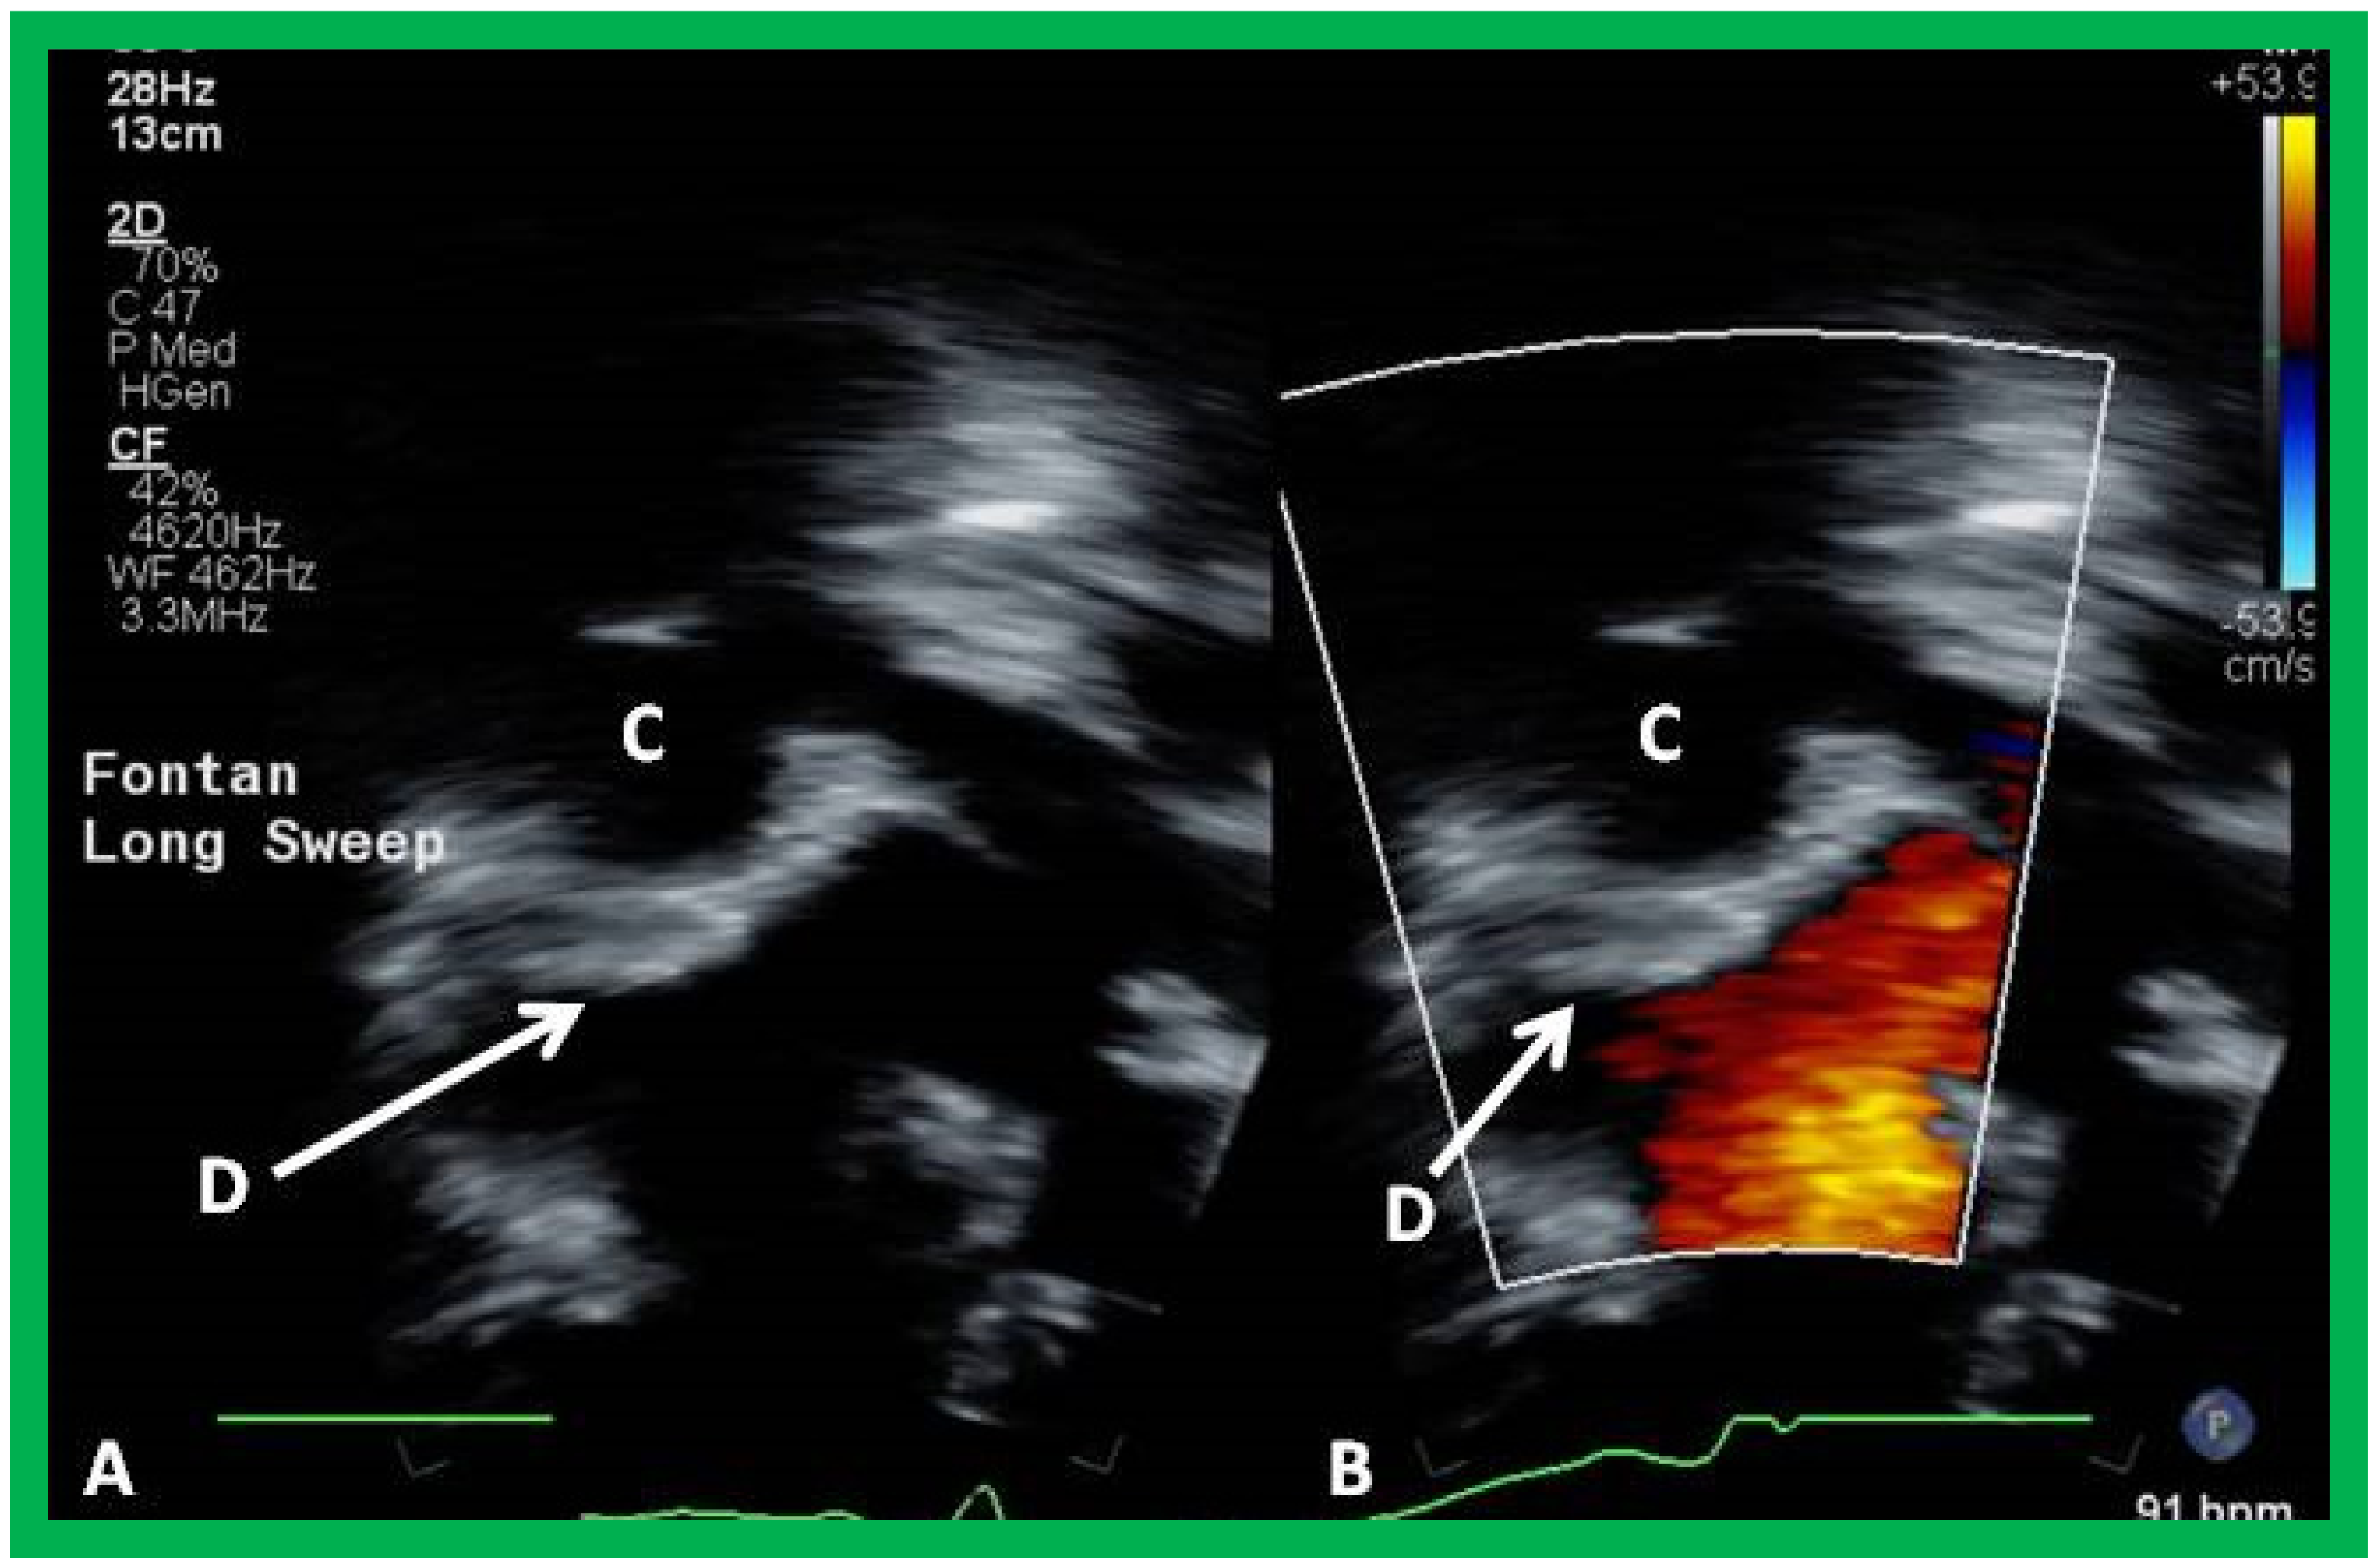

10.4.1. Stage IIIA

10.4.2. Stage IIIB